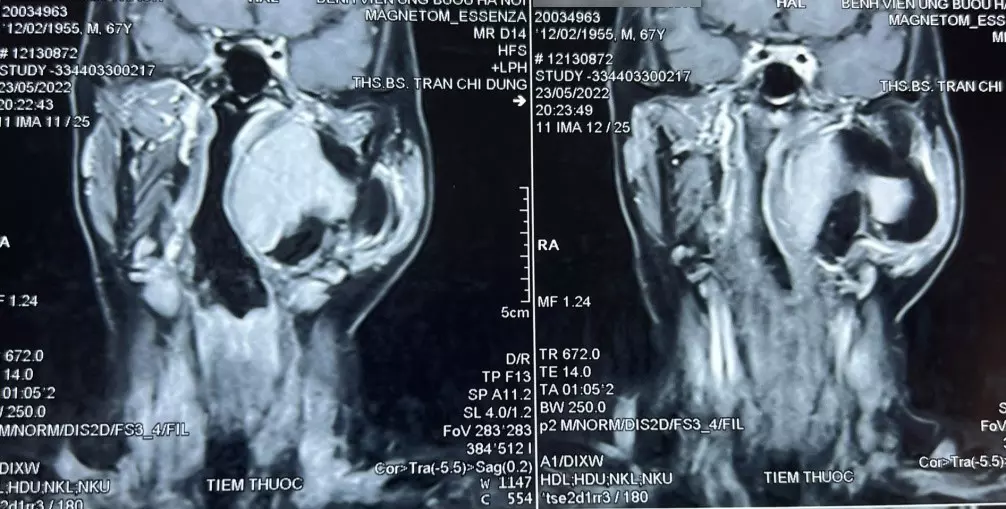

Bệnh nhân đến khám vì khối sưng phồng vùng mang tai trái, không kèm theo khó chịu hay đau đớn. Qua thăm khám, bác sĩ phát hiện một khối u lớn vùng cổ kích thước khoảng 10 x 8 cm, thuộc khoảng bên họng, trải dài từ nền sọ xuống hạ họng, đẩy lệch thành bên họng vào trong. Khối u gồm 2 phần, phần nông nằm dưới tuyến mang tai và phần còn lại nằm sâu hơn.

Hình ảnh chụp cộng hưởng từ khối u khoảng bên họng của bệnh nhân.